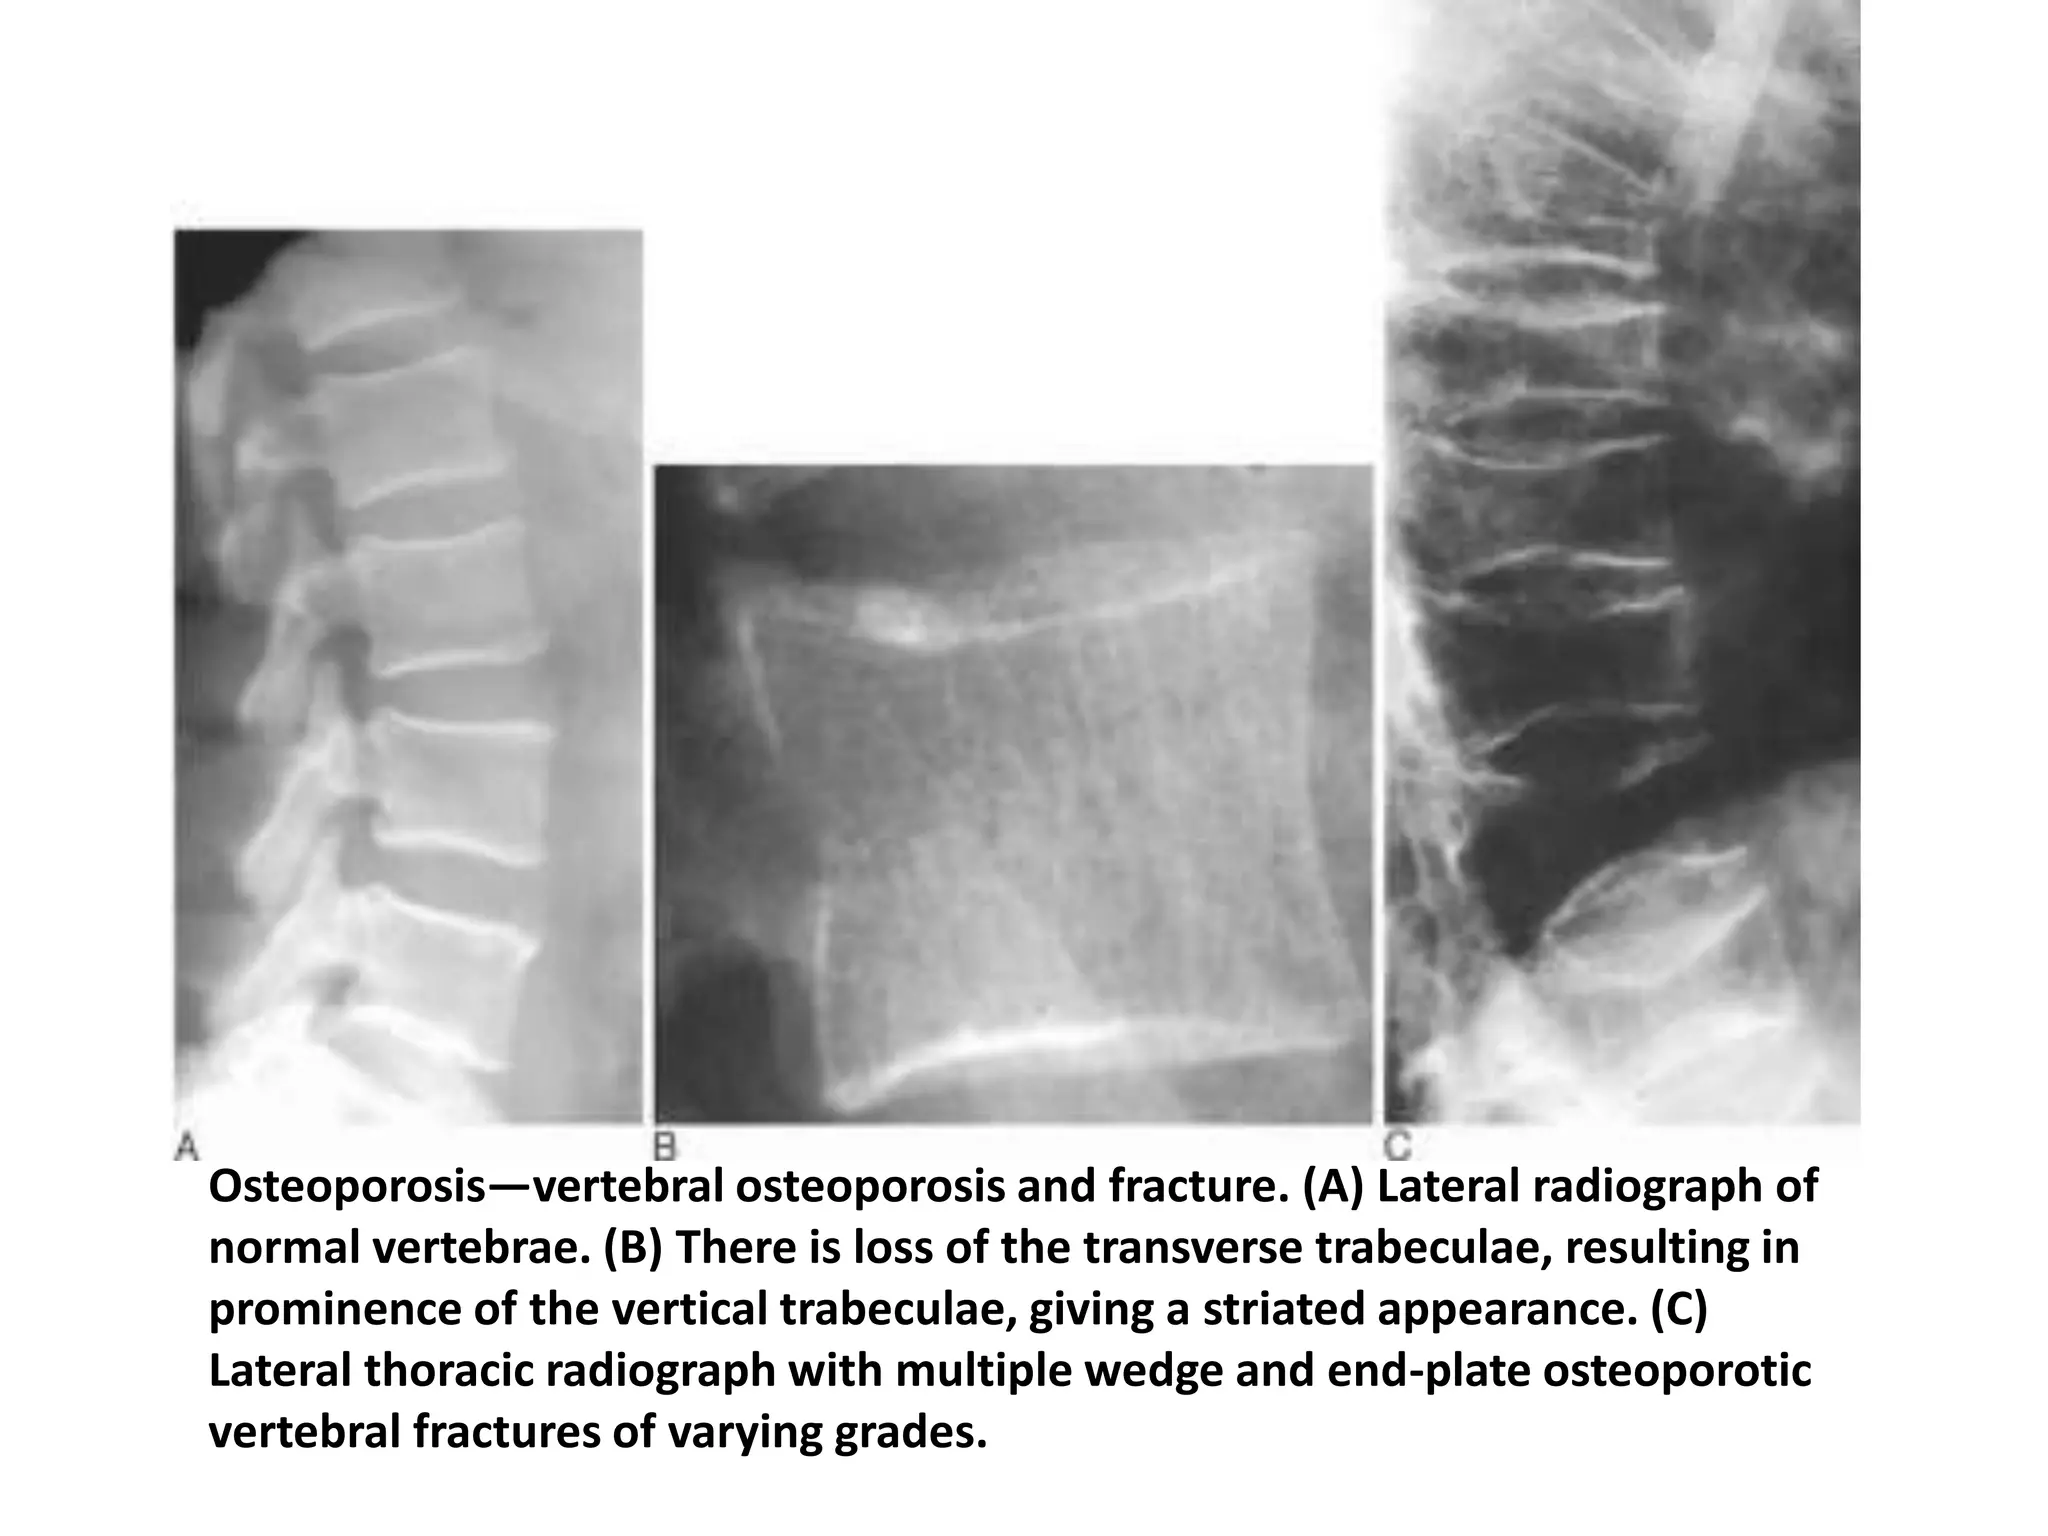

Spine:

•Vertical striated appearance to several vertebral body on lateral

radiograph.

•Vertebral fracture

Osteoporosis—vertebral osteoporosis and fracture. (A) Lateral radiograph of

normal vertebrae. (B) There is loss of the transverse trabeculae, resulting in

prominence of the vertical trabeculae, giving a striated appearance. (C)

Lateral thoracic radiograph with multiple wedge and end-plate osteoporotic

vertebral fractures of varying grades.